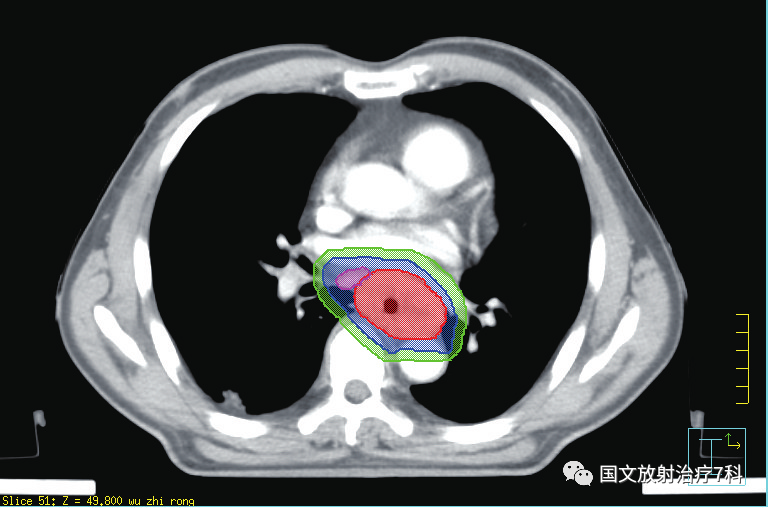

第二步,CT模擬定位。在扣膜狀態(tài)下進(jìn)行CT平掃+增強(qiáng)掃描,獲取影像后放療科醫(yī)生就可以在電腦上借助軟件進(jìn)行靶區(qū)的勾畫(huà)了。

第三步,勾畫(huà)靶區(qū)之后,醫(yī)生需要提交治療計(jì)劃,與醫(yī)學(xué)物理師共同完成對(duì)靶區(qū)劑量的設(shè)定,以及危及器官受量的限定。物理師需要借助電腦軟件精確腫瘤患者的放療物理范圍,獲得最優(yōu)的物理劑量分布,做出一個(gè)讓放療醫(yī)生滿意的放射治療方案,為腫瘤患者“對(duì)癥下藥”。 簡(jiǎn)單來(lái)講,就是讓射線最大量的照射在靶區(qū)上,最大程度地控制周邊需要保護(hù)器官的射線劑量。靶區(qū)勾畫(huà)和治療計(jì)劃確認(rèn)依病情的復(fù)雜程度一般需要3-7天,需要患者的耐心等待。醫(yī)學(xué)物理師是臨床醫(yī)師和大型精密治療器械的銜接單位,有強(qiáng)大的醫(yī)學(xué)物理師團(tuán)隊(duì)是對(duì)治療的充分保障。